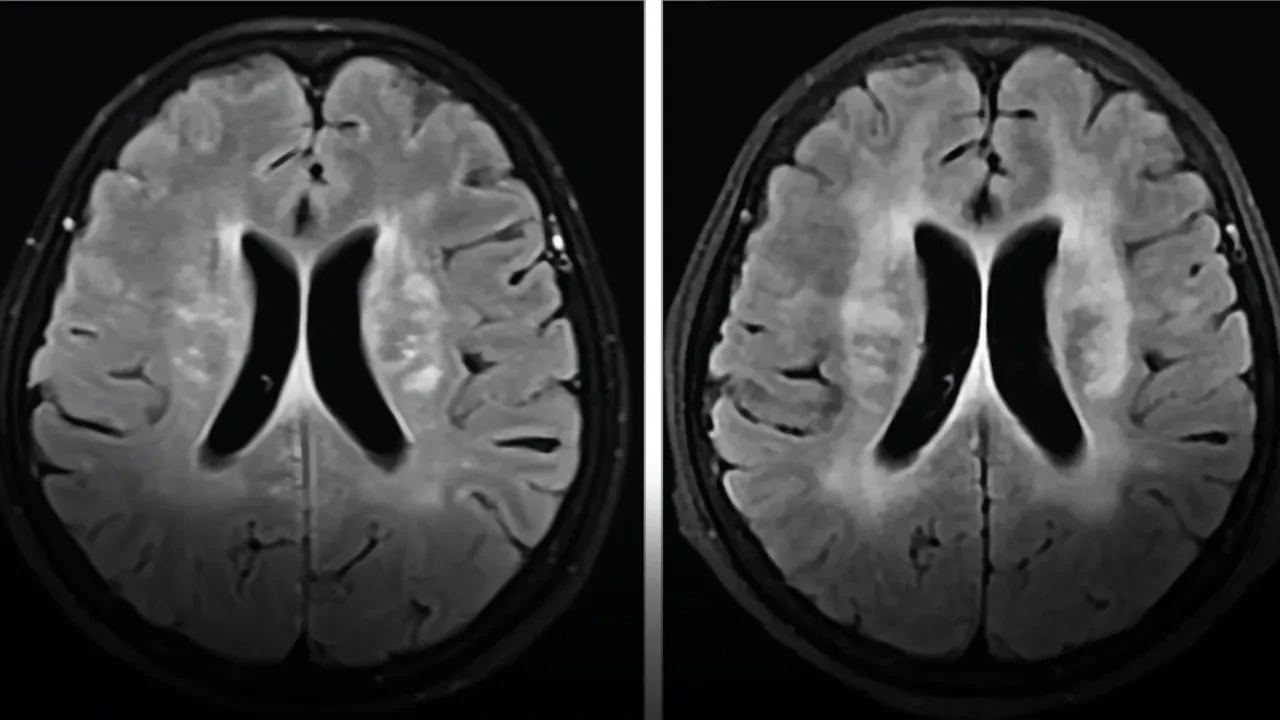

Həkimlər əvvəlcə meningit şübhəsi ilə hərəkətə keçiblər. Müayinələr nəticəsində onun beynində çoxlu zədələr aşkarlanıb ki, bu da yoluxma ehtimalını gücləndirib. Lakin iki həftəlik antibiotik müalicəsinə baxmayaraq, xəstənin səhhətinin vəziyyəti getdikcə pisləşib.

Xəstəyə dərhal antiparazitar dərman verildi. Xəstə iki həftə ərzində danışıq qabiliyyətini bərpa etdi və səhhəti sürətlə yaxşılaşdı. Dörd aydan sonra nəzarətlər göstərdi ki, beyindəki zədələr əhəmiyyətli dərəcədə azalıb və xəstə demək olar ki, tamamilə sağalıb.